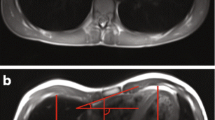

For this prospective study, all patients with pectus excavatum between 6 and 30 years of age, who presented for chest wall deformities in the Department of Pediatric Surgery between January 2020 and June 2021, were included. Real-time MRI of the thorax was performed to determine the thoracic dimensions and indices HI, CI, AI, and EI. Exclusion criteria included contraindications to MRI, such as claustrophobia and carrying metallic or electronic implants incompatible with MRI. Patients with a sterno-vertebral distance of less than 5 mm were excluded, assuming that the limited spatial resolution would have a considerable impact on index measurement (Fig. 1). The study was approved by the Institutional Review Board (169–20ek), and written consent was obtained from all subjects or their legal guardians.

After the localizer sequences for spatial orientation and identification of the deepest point of deformity, the protocol employed a dynamic real-time fast low-angle shot (FLASH) MRI sequence which simultaneously provided a sagittal and transverse image series in a frame-interleaved manner. After previous coaching of the patient (Supplemental Table 1), the measurement involved two sequential scans to monitor both quiet and forced breathing during periods of 13 s (corresponding to 2 × 200 frames). The experimental parameters included repetition time, 2.22 ms; echo time, 1.44 ms; 15 radial spokes; flip angle, 8°; slice thickness, 6 mm; field of view, 320 × 320 mm2; in-plane resolution, 1.6 × 1.6 mm2; and acquisition time per frame, 33.3 ms. The total examination time for the study sequences was 3 min, including scout sequences and teaching of breathing commands (MRI exam protocols are available as Supplemental Files). As a typical example, Supplemental Video 1 shows simultaneously acquired sagittal and transverse MRI movies of a patient with funnel chest during forced breathing.

For quiet and forced breathing conditions, the dimensions required for calculating the thoracic indices HI, CI, AI, and EI were determined from transverse images at the deepest point of the funnel (Fig. 1). This task was performed by a pediatric radiologist (D.G., 12 years of experience in pediatric MRI) with use of a conventional DICOM Viewer (syngo.plaza, Siemens). For assessment of interobserver variability, the analysis was independently performed by a study nurse (I.K., 8 h of training). Values of HI > 3.25 and CI > 28% were presumed as pathological according to the literature [14]. A correlation analysis between HI and CI was performed. Modified AI and EI measures (Fig. 1) were introduced to account for different lateralities, with 1 being subtracted from the ratio of larger diameter and smaller diameter. Right laterality was tagged with a negative sign.

Index variation during breathing

All thoracic indices showed significant differences (Δ) between maximal inspiration and maximal expiration (Fig. 2). During exhalation, HI was found to be higher in 55 subjects (98%), while CI was lower for 14 (25%). The impact of breathing resulted in 4 subjects (7%) having HI values above the pathologic threshold of 3.25 and 15 subjects (27%) passing the CI threshold of 28%. Figure 3 shows the median absolute deviation of the thoracic indices during forced expiration, which were ΔHI = 1.1 (0.7–1.6, p < .001), ΔCI = 4.8% (1.3–7.5%, p < .001), ΔAI = 3.0% (1.0–5.0%, p < .001), and ΔEI = 8.0% (3.0–14.0%, p < .05). The correlation between HI and CI was weak (r2 = 0.49, p < .001) (Fig. 4). The interrater variability for the assessment of the morphologic indices was excellent, with intraclass correlation coefficients being 0.98 for HI, 0.97 for CI, 0.95 for AI, and 0.94 for EI. There was no significant correlation between HI and ΔCI, ΔAI, or ΔEI. Neither was found a correlation between age of the patient and the chest indices.